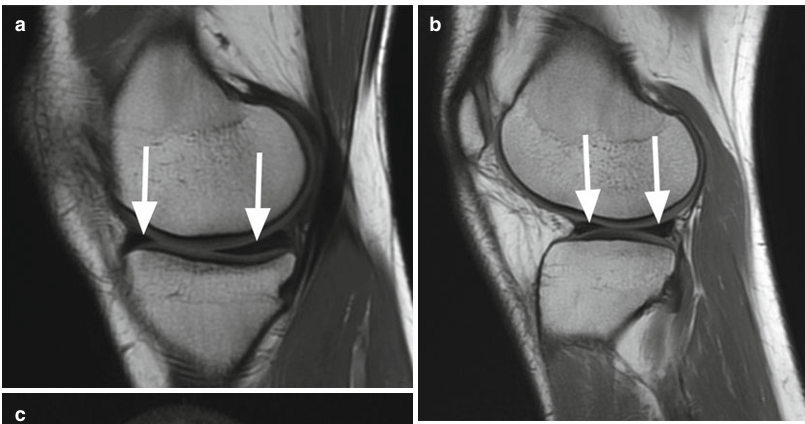

Fig. 5.1 Meniscos normales en una mujer de 19 años. La imagen de FSE de densidad de protones sagitales (PD) a través del departamento medial ( a ) muestra el menisco medial que es más ancho posteriormente que anteriormente ( flechas ). Imagen de FSE de protones sagitales (PD) a través del compartimento lateral